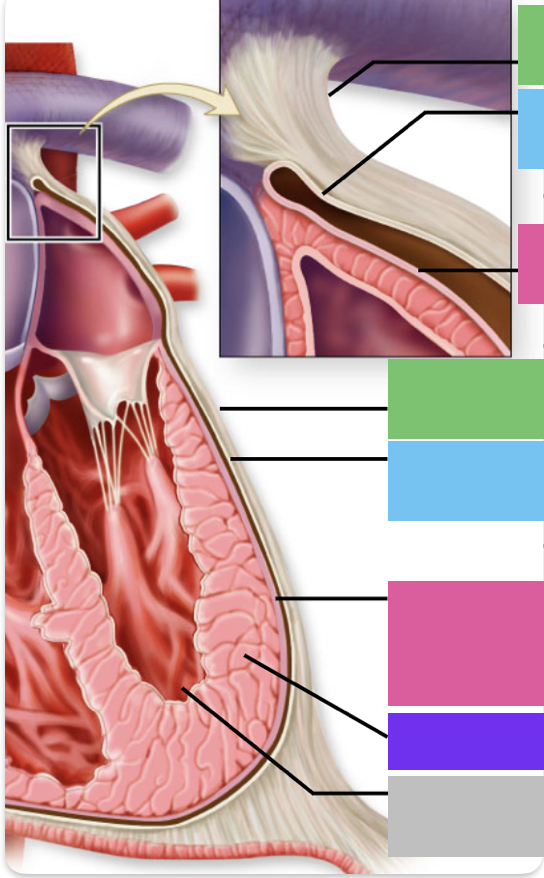

chordae tendineae

orange

papillary m.

blue

trabeculae carneae - only in ventricles

red

pectinate m. - only in R atrium

pink

fossa ovalis

grey

opening of coronary sinus